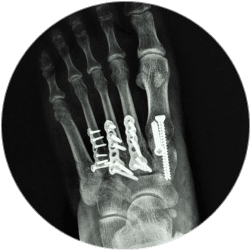

Хирург проводит фиксацию костных структур, используя металлоконструкции, проверяет правильность проведенных действий, ставит дренаж (если требуется).